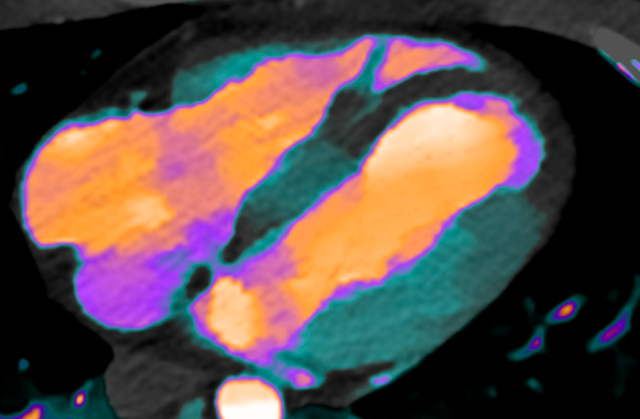

Here is a color image of the same:

Notice the extremely dark area at the apex and apical part of the septum.

The radiologist was Dr. Gopal Punjabi, who is quite a wizard, and frequently diagnoses acute MI on CT scan of the chest. He immediately saw this and notified the clinicians.